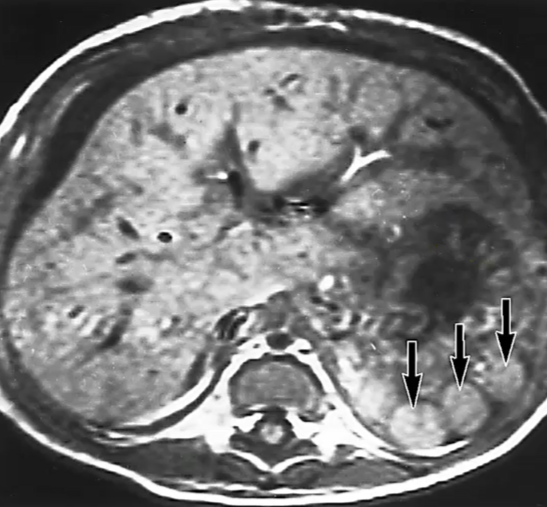

What does Gaucher's disease look like on ultrasound?

Extremely enlarged spleen with heterogeneous texture

Multiple focal hypoechoic nodules